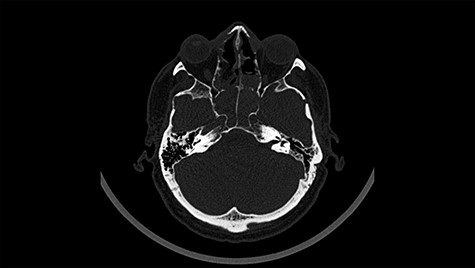

Head CT after polypectomy—seen defects of the upper left orbital wall. (Department of Neurosurgery own material).

In described case, a head CT scan after polypectomy confirmed the subarachnoid hemorrhage (Fig. 1). In addition, the presence of air in the ventricular system was visible, and presence of defects of the upper left orbital wall and ethmoid on both sides (Fig. 3). In the CT scan sphenoid sinus, frontal and ethmoidal sinuses on both sides and right maxillary sinus airless, filled with blood and soft tissue. The changes also concerned the lateral part of the left maxillary sinus (Fig. 4).

The present bone defects were most probably caused by the development of osteomalytic foci as a consequence of the spread of the inflammatory process within the diploe of flat skeletal skull bones, in the course of chronic rhinosinusitis. Both underestimating the severity of complaints in the course of chronic rhinosinusitis and delaying the implementation of surgical treatment led to massive bone destruction, which had an impact on the development of further complications after polypectomy (including subarachnoid hemorrhage). Performed angio-CT excluded any malformations and the probable cause of subarachnoid hemorrhage due to rupture of the aneurysm. Considering the radiological picture and the condition of the patient, it can be concluded that the persistent inflammatory process within sinuses led to dehsomination and subsequent bleeding into the subarachnoid space through discontinuity in the bone structure of the sinuses and orbits.